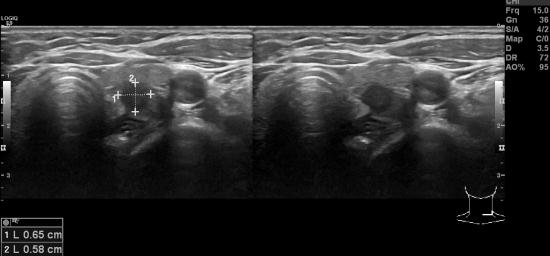

유방암 수술후 재발 검사위해 시행한 PET scan상

갑상선에 이상소견 의심되어

본원에서 갑상선 초음파 및 미세침흡인세포 검사 시행하셨습니다.

갑상선의 유두상 암으로 나왔으며

다행이 크기는 0.6cm정도로 수술로 완치가 될 정도로 예후가 좋은

경우라 마음이 덜 무겁습니다.